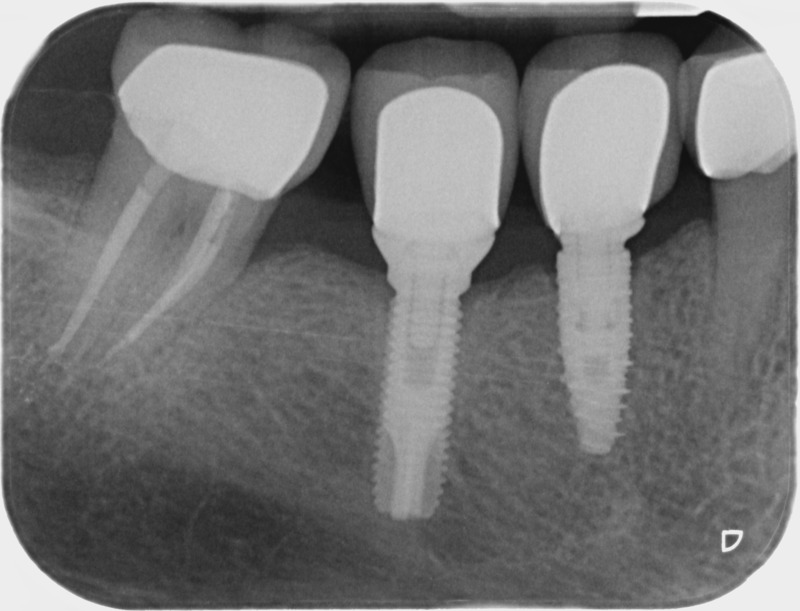

• Couronnes sur implants : Lorsqu’un implant est posé en remplacement des racines d’une dent, il est conçu pour recevoir d’abord un pilier vissé puis une couronne céramique. Le couple couronne - implant se substitue à la dent manquante pour en assurer les mêmes fonctions. Nous pouvons également adapter un bridge sur plusieurs implants dans le cas d’un édentement plus important.

Après